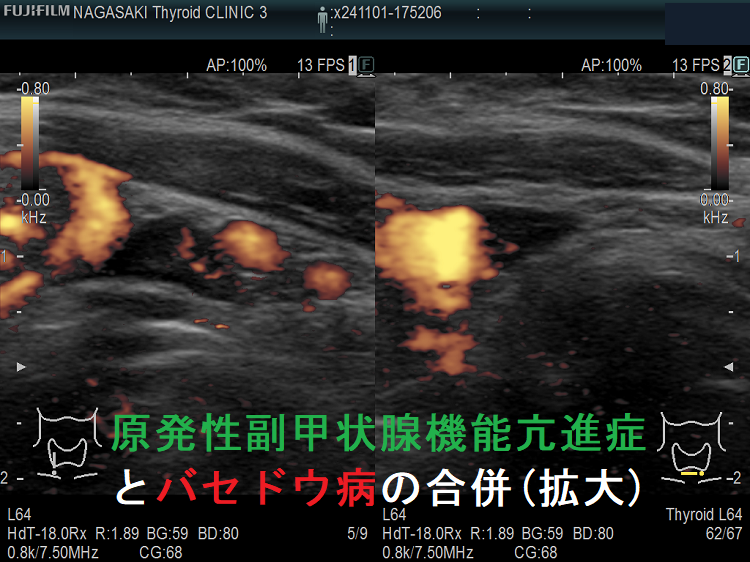

また、原発性副甲状腺機能亢進症とバセドウ病が合併するケースもあります。初診時に高カルシウム血症を認めるも、副甲状腺ホルモン(PTH)は正常値なので、甲状腺機能亢進症/バセドウ病による高カルシウム血症と診断されます。しかし、甲状腺機能が正常化した後も高カルシウム血症が持続するため、改めて副甲状腺ホルモン(PTH)を測定すれば高値を示します。甲状腺機能亢進時の99mTc-MIBI シンチグラフィーには疑わしいhot spot を認めますが、確定的ではありません。筆者の考えですが、初診時は甲状腺機能亢進症/バセドウ病による高カルシウム血症が副甲状腺腫を抑制していたのではないでしょうか?[Quant Imaging Med Surg. 2022 May;12(5):3014-3019.]